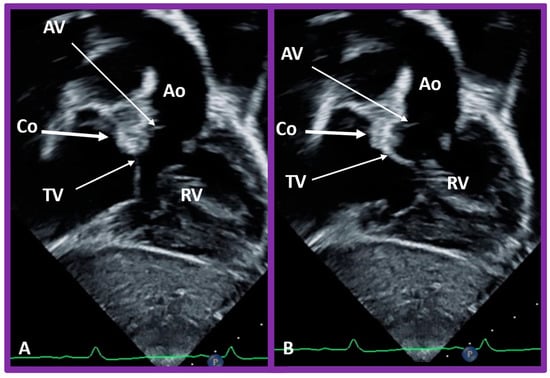

The position of the conal tissue relative to the pulmonary and aortic valves is characterized as subpulmonary or subaortic, or it may be present beneath both the semilunar valves, or it may be absent bilaterally. The conal tissue displaces the semilunar valve anteriorly and superiorly; the more conus tissue underneath a semilunar valve, the more superior and anterior that semilunar valve is displaced. Therefore, superior to inferior and anterior-to-posterior relationships of the semilunar valves indicate conal anatomy. In normal subjects, the conus is subpulmonary (Figure 31 and Figure 37C). In patients with transposition, subaortic conus is seen whether it is d-transposition (Figure 35 and Figure 36) or l-transposition (Figure 40, Figure 41 and Figure 51). Bilateral conus is seen in DORV (Figure 48B and Figure 49B), and the conus is absent in the double-outlet left ventricle. The conal tissue and superior and anterior dislocation of the semilunar valves can be easily ascertained by echo imaging (Figure 31, Figure 35, Figure 36, Figure 37C, Figure 40, Figure 48B, Figure 49B and Figure 51) and may also be evaluated similarly if other imaging studies are performed.

Figure 51. Selected video frames in subcostal views to demonstrate the atrioventricular valve-to-semilunar valve relationship in a child with l-transposition of the great vessels demonstrating a lack of continuity between the aortic valve (AV) and tricuspid valve (TV) leaflets due to conus (Co) separating them. The TV closed in (A) and open in (B). Ao, aorta; Right ventricle (RV).